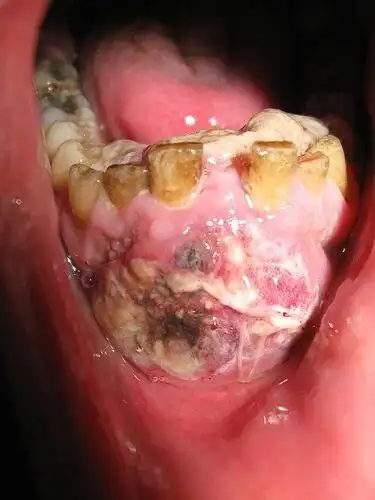

口腔溃疡90%会恶化成口腔癌,这是真的吗?

这种口腔溃疡可能是口腔癌口腔癌的几大征兆你中了吗

警惕"口腔溃疡"!鲁东医院成功完成一例下颌牙龈恶性肿瘤根治术

口腔溃疡老是反反复复,警惕:超两周不愈当心"口腔癌"!_习惯_进行_图片

槟榔成瘾者自述:为了戒槟榔,把最恶心的口腔癌图片当桌面